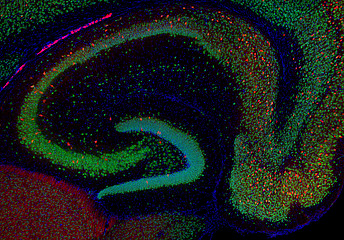

Channeling our research efforts towards understanding hippocampal brain development has proven to be a pivotal strategy in unraveling the intricate mechanisms that shape memory, learning, and spatial navigation. The hippocampus plays a central role in cognition and has emerged as a focal point in the study of brain development. As a brain region with lifelong plasticity insights into the hippocampal physiology are valuable for many other areas of the brain – their development, connectivity, function, and dysfunction.